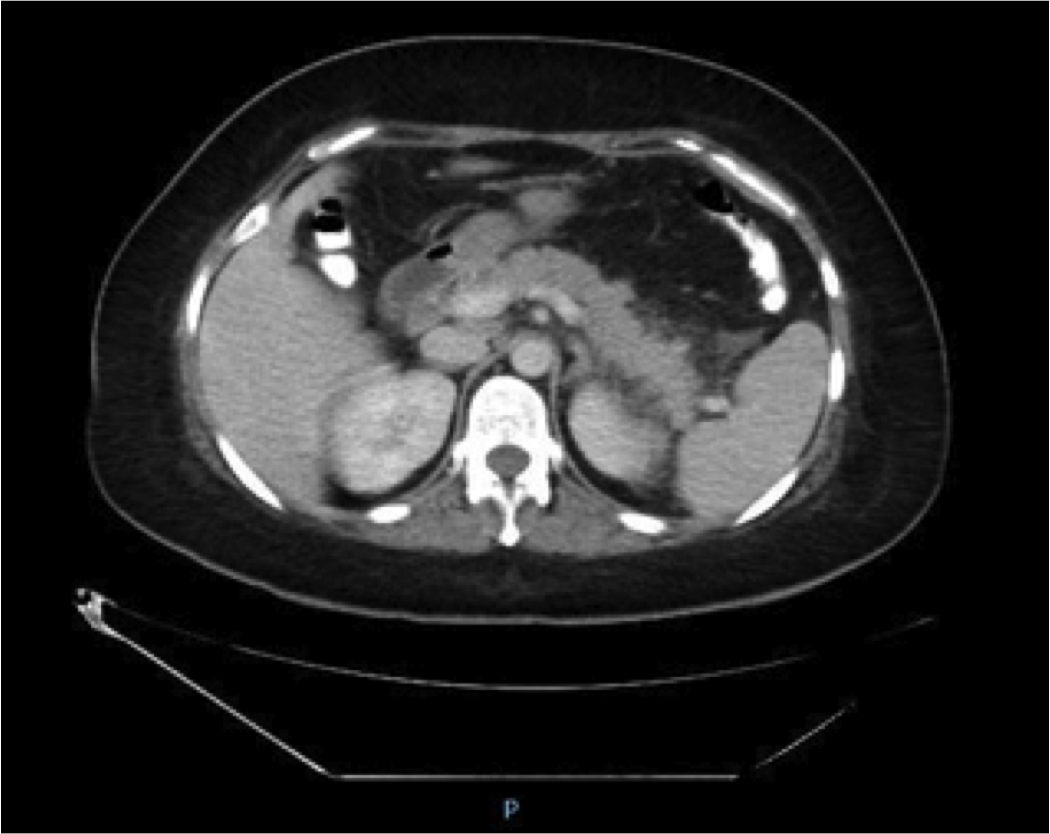

Case Presentation: A 41-year-old female presented with symptoms of abdominal pain, nausea, and vomiting one week after starting Methimazole 10 mg daily for Graves’ disease. She had no prior history of alcohol use or cholelithiasis. Her physical examination was significant for tenderness to superficial and deep palpation in her epigastrium. Her labs revealed a lipase level of 2457 (14-60) with normal liver function tests, normal triglyceride and calcium levels. Ultrasound of her abdomen showed no gallstones. CT scan of her abdomen confirmed a diagnosis of acute pancreatitis with evidence of pancreatic tail fat stranding. MMI was stopped on admission and other causes of acute pancreatitis were ruled out based on history, clinical presentation, labs, and imaging. She was treated with aggressive fluid resuscitation and kept NPO due to nausea. Intravenous opioid analgesics were administered to control her abdominal pain. Patient responded well to supportive therapy after discontinuation of MMI. She was re-challenged with MMI two days later with recurrence of symptoms including abdominal pain, nausea, and vomiting. A repeat elevated lipase level of 204(14-60) was noted. MMI was discontinued once more with complete resolution of her symptoms. In order to continue management of her Graves Disease, she was started on Propylthiouracil(PTU), Propranolol, and Dexamethasone. There is no known cross reactivity between PTU and MMI in causing acute pancreatitis. The patient eventually underwent a total thyroidectomy. She remained symptom-free through the rest of her hospitalization and was discharged home after being started on Levothyroxine.